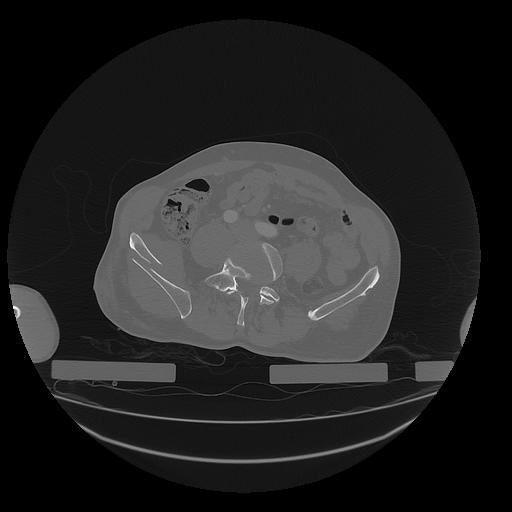

31 PULMON,CE,Vol,1.0,PULMON,,